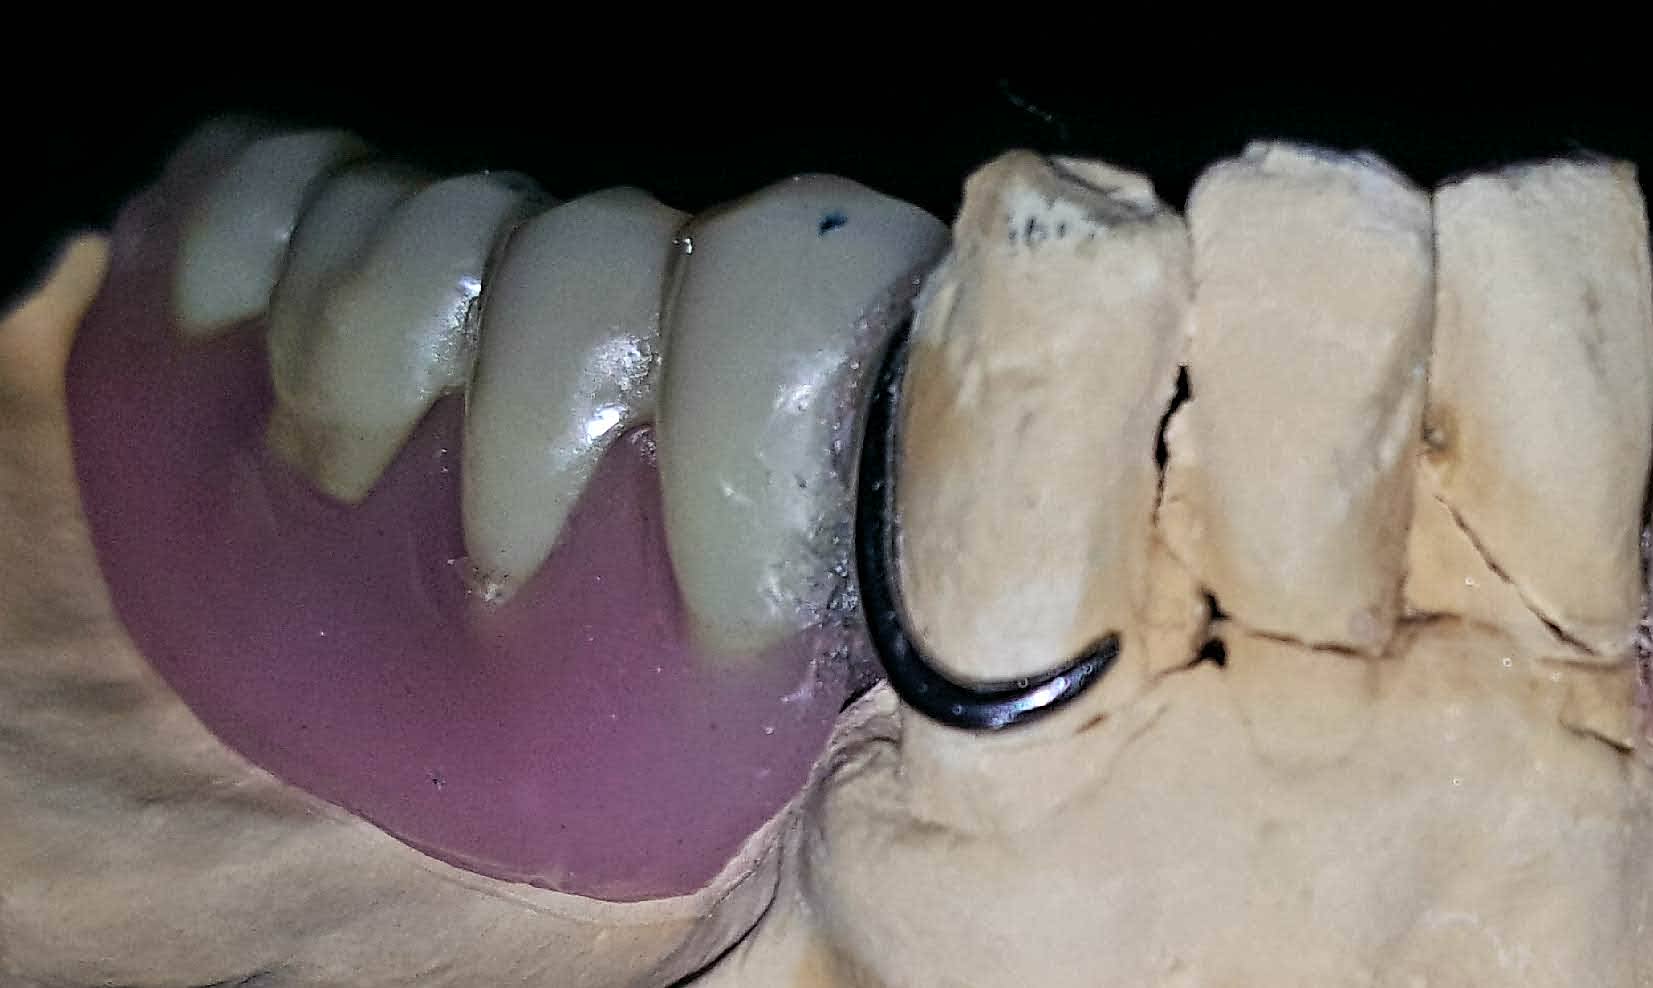

Avant... je laissais mon protho couler mes empreintes secondaires de stellites (perso, je suis un maniaque de mes empreintes...)

Alors je fais adhésif fix de chez sirona sur PEI + alginate neocolloid + hurrimix +eau distillée...

Et regarde ce que je recois hier d'un protho local: ca me coute cher pour rien... je paies le prix audi pour recevoir du dacia. Je sais meme pas si c est un platre classe iv... des economie de bout de chandelle pour des prix premiums.